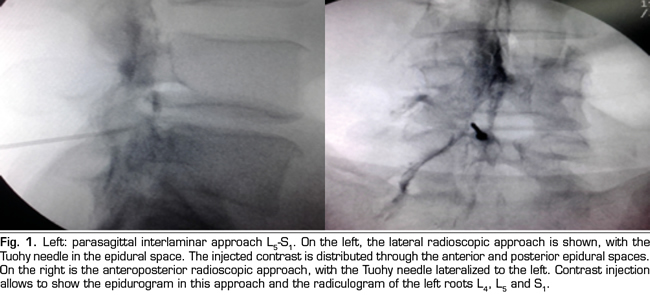

The procedure was performed in the surgical room. A peripheral venous catheter was placed with the patient on ventral decubitus position. Asepsis was conducted with alcoholic chlorhexidine and the local anesthesia was performed with 0.5 % lidocaine. Eighteen 3 1/2 or 4 3/4 inches tuohy needles (depending on patient size) were used for the parasagittal interlaminar technique. In the anteroposterior radioscopic view, the needle was inserted into the L4-5 or L5-S1 interlaminar spaces, using the tunnel vision technique, homolateral parasagittal of the side corresponding to the radicular pain (Figure 1). Loss of resistance was performed with saline. In the lateral view, a 4 mL contrast injection (Omnipaque©) was administered and the presence of anterior, posterior or both epidurograms was recorded (Figure 1). In the anteroposterior view the presence of radiculogram was recorded (Figure 1). A vial of betamethasone (12 mg of a mixture of phosphate and betamethasone acetate in 2 mL of solution) was then administered diluted with 3 mL of 0.5% lidocaine (total solution: 5 mL). The technical quality of the procedure was determined with the presence of paresthesia or concordant pain during the injection, and radiological data such as presence of radiculogram (Figure 1). Twenty two, 3 1/2 or 4 3/4 inches quincke needles were used in the transforaminal group and inserted using the oblique, lateral and anteroposterior radiological views.

The technical quality of the epidural steroid injection was evaluated in 21 out of 26 procedures performed with the parasagittal interlaminar approach. Anterior epidurograms, that is, achievement of the solution on the ventral epidural space, was obtained in 15 (71 %) of the patients (Figure 1 left); 17 (85 %) patients referred pain or paresthesia in the radicular territory during the injection, and a radiculogram was found in 12 (60 %) patients.